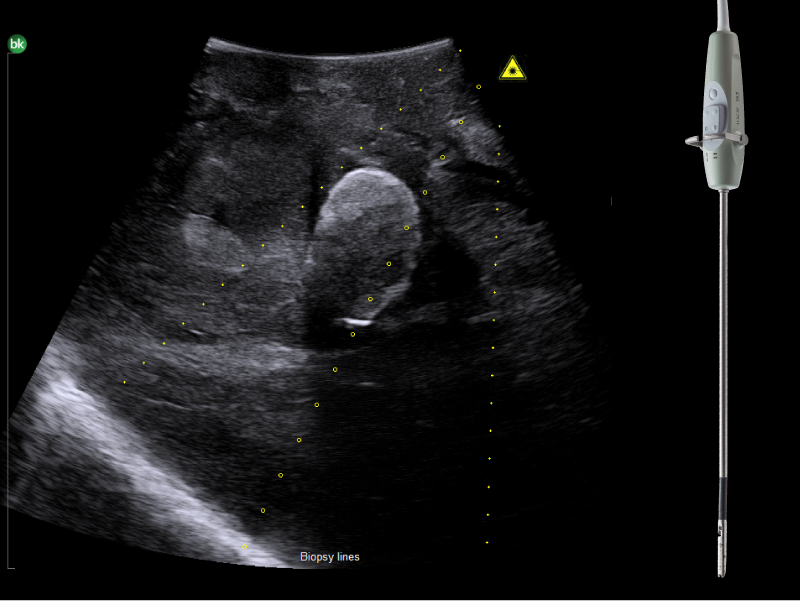

Pancreatic head mass, visualized with Biplane Transducer